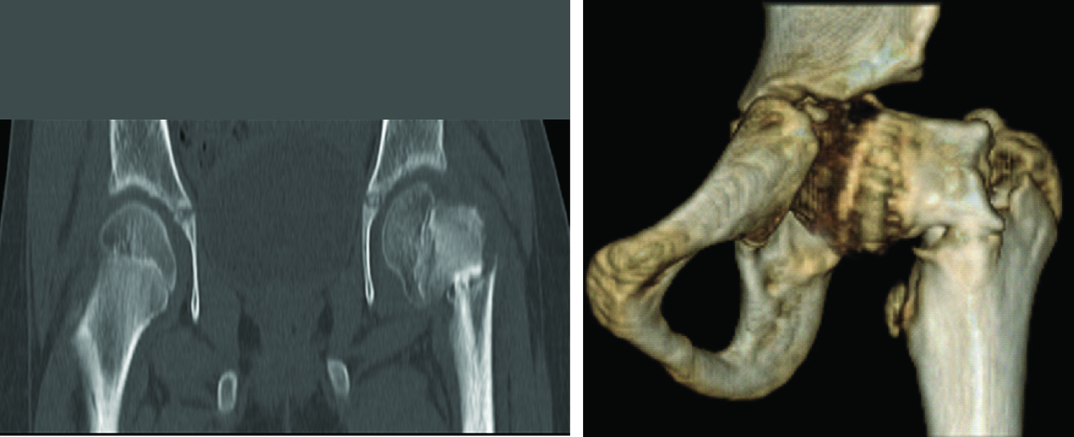

CT-scan: Revealed fracture neck of left femur with non-union, with sclerosis of the fracture ends [Table/Fig-2a,b].

CT-scan showing non-union with varus deformity.